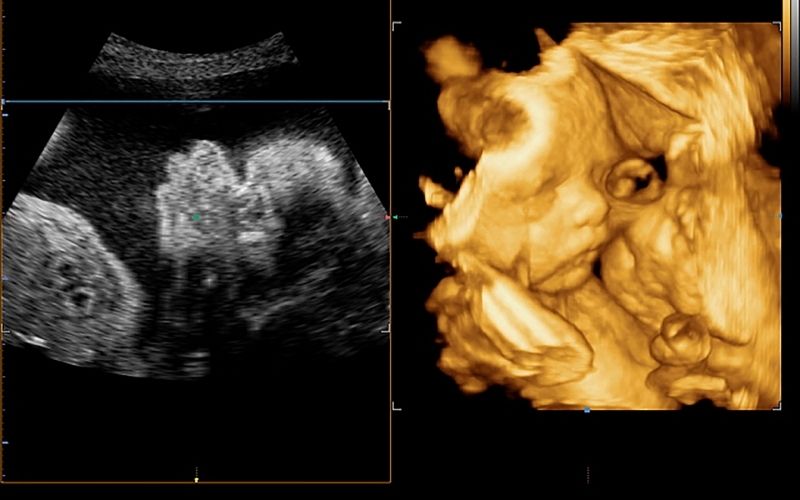

Biến chứng tiểu đường thai kỳ nguy hiểm cho thai nhi

Một số nguy hiểm mà bệnh tiểu đường thai kỳ có thể gây hại cho thai nhi gồm:

Sảy thai, thai chết lưu không rõ lý do.

Nguy cơ thai nhi bị dị tật bẩm sinh.

Trẻ sinh ra bị tụt canxi, hạ đường huyết, suy hô hấp, nguy cơ mắc bệnh tiểu đường di truyền.

Tỉ lệ tử vong sau sinh do thai quá to khó sinh, biến chứng tiểu đường thai kỳ tăng cao.